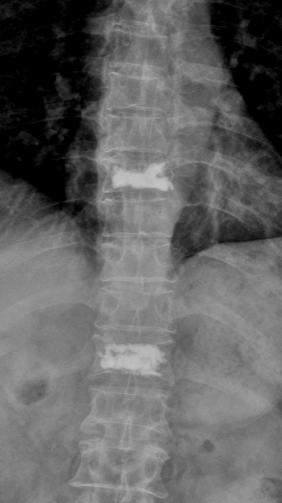

术前核磁共振检查明确T8.12椎体骨折,为疼痛责任椎体;经皮穿刺微创椎体成形术后复查可见椎体高度恢复良好,骨水泥弥散满意。

自2019年我院创伤外科“精细化椎体成形治疗老年骨质疏松性压缩骨折”获得广州市临床特色项目以来,在医院的大力支持下,刘志祥主任团队追求卓越的步伐从未歇息,对此项技术的检查方法及手术技巧进行了进一步的钻研,以更熟练的技术和更小的创伤为更多的老年性骨质疏松椎体骨折患者解除痛苦。通过术前过伸位X线检查,为无MRI设备基层医院或身体原因无法行MRI检查患者,提供新的检查手段,以便早期诊断、早期治疗。术前对伤椎3D打印模型仔细研究,模拟穿刺方向、深度等,根据不同患者骨折类型,制定个性化穿刺路径,减少穿刺损伤风险和手术时间等,有效减轻疼痛和快速康复。正如刘志祥主任期待,老年骨质疏松性患者能够得到更科学、更微创、更规范的治疗,有效解决疼痛,恢复日常生活,并有效避免再次骨折。

术前过伸位X、CT检查,早期诊断